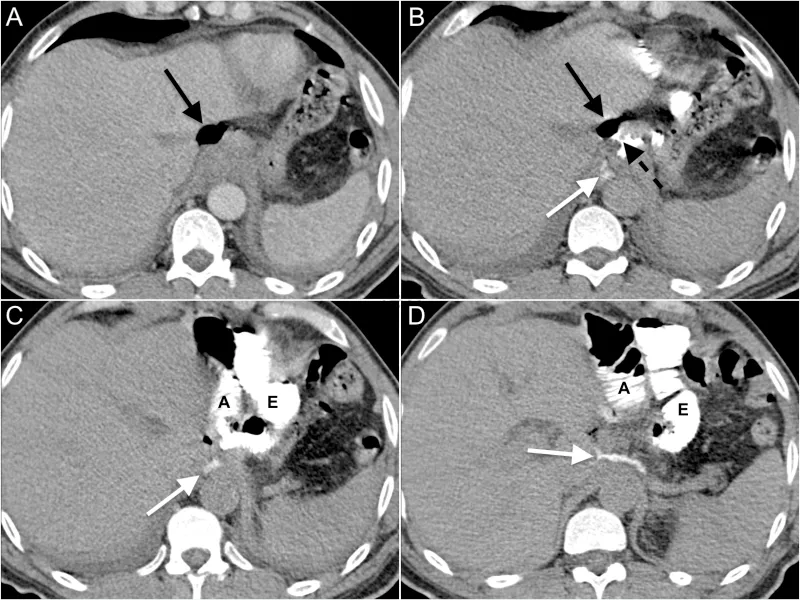

- CT Scan (Abdomen/Pelvis) with Contrast:

- IV contrast: Identifies abscesses, inflammation, and perfusion defects.

- Oral or Rectal contrast: (Water-soluble, e.g., Gastrografin) Directly visualizes contrast extravasation from the lumen.

- CT scan with oral or rectal contrast is the diagnostic gold standard, showing fluid collections or contrast extravasation.